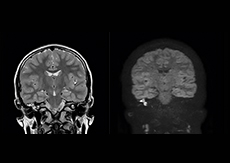

“We have compared image quality of FLAIR with MultiVane XD versus FLAIR without MultiVane XD. In 15 of the 40 patients studied, we saw motion artifacts on plain FLAIR brain images. The FLAIR images with MultiVane XD were motion-free in 39 of 40 patients and showed slight motion artifacts in only one patient.”